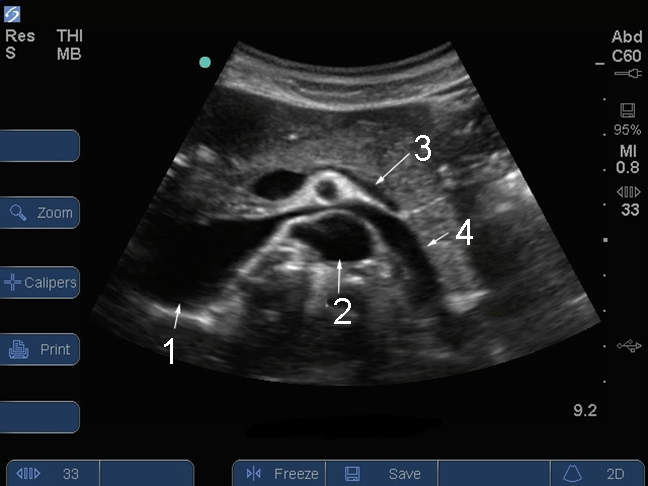

M-Turbo: Vista abdominal transversal de páncreas, aorta y VCI

1. Vena cava inferior (VCI)

2. Aorta (Ao)

3. Vena esplénica

4. Vena renal izquierda (VRI)